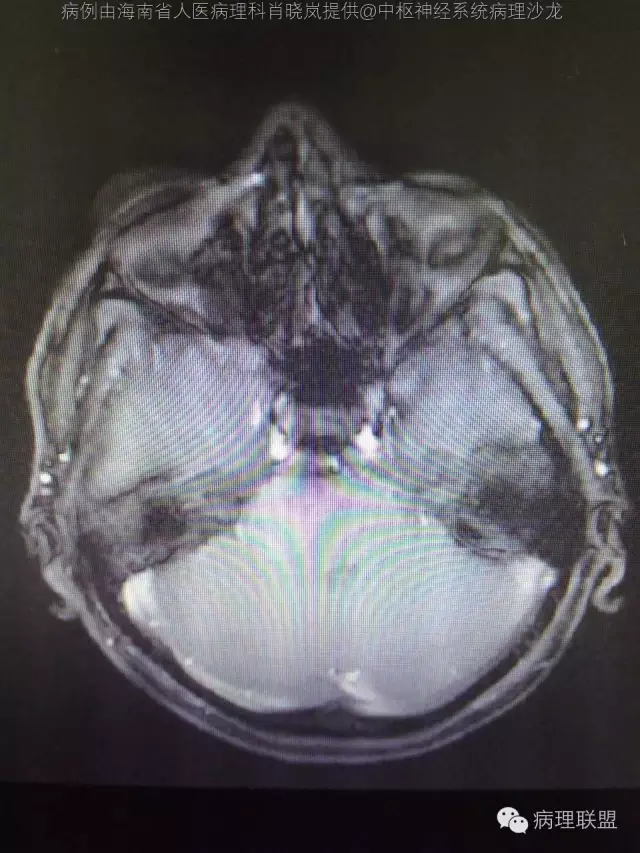

男,36岁。右面部麻木1月余。手术所见:右CPA区见5Ⅹ4cm肿块,灰褐色,血供丰富,质韧,界清。临床诊断:右侧桥小脑角区占位:脑膜瘤。大体检查:灰黑色碎组织一堆,大小2.5Ⅹ2.5x0.5cm,免疫S100,HMB45阳性。Ki67指数低。(病例由海南省人医病理科肖晓岚提供,致谢!)

@海南省人医病理科肖晓岚 影像也是符合黑色素相关肿瘤,可请影像专业的老师分析一下CT结合MR对产生黑色素的病变还是具有一定的特征性的,本例黑色素含量似乎不太多,所以跟脑膜瘤差不太多了,需要请影像老师分析!